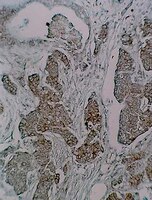

| Novel agents that downregulate EGFR, HER2, and HER3 in parallel. Ferreira, RB; Law, ME; Jahn, SC; Davis, BJ; Heldermon, CD; Reinhard, M; Castellano, RK; Law, BK

Show Abstract

EGFR, HER2, and HER3 contribute to the initiation and progression of human cancers, and are therapeutic targets for monoclonal antibodies and tyrosine kinase inhibitors. An important source of resistance to these agents arises from functional redundancy among EGFR, HER2, and HER3. EGFR family members contain conserved extracellular structures that are stabilized by disulfide bonds. Compounds that disrupt extracellular disulfide bonds could inactivate EGFR, HER2, and HER3 in unison. Here we describe the identification of compounds that kill breast cancer cells that overexpress EGFR or HER2. Cell death parallels downregulation of EGFR, HER2, and HER3. These compounds disrupt disulfide bonds and are termed Disulfide Bond Disrupting Agents (DDAs). DDA RBF3 exhibits anticancer efficacy in vivo at 40 mg/kg without evidence of toxicity. DDAs may complement existing EGFR-, HER2-, and HER3-targeted agents that function through alternate mechanisms of action, and combination regimens with these existing drugs may overcome therapeutic resistance. |  |  | 25865227  |